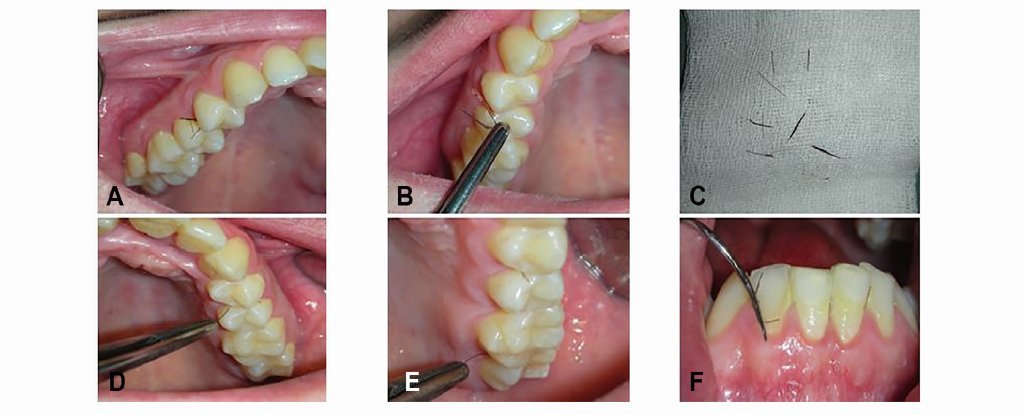

În termeni comuni, hirsutismul gingival este o condiţie medicală care se manifestă prin creşterea unor fire de păr asemănătoare genelor din ţesuturile moi care pot fi identificate în cavitatea bucală. Medicii care au raportat acest caz au efectuat şi o trecere în revistă a literaturii legate de această afecţiune şi au descoperit doar alte cinci cazuri asemănătoare, pacienţii fiind cu toţii bărbaţi.

Iniţial, medicii au decis îndepărtarea firelor de păr, urmată de administrarea unor contraceptive orale pentru restabilirea echilibrului hormonal. După şase ani, timp în care tratamentul hormonal a fost întrerupt, femeia s-a prezentat din nou la clinica unde a fost tratată prima dată.

Medicii au decis ca în timpul procedurii de îndepărtare a firelor de păr să preleveze şi mostre din ţesuturile din care creşteau respectivele fire. În urma analizării acestor mostre, oamenii de ştiinţă au ajuns la ideea că ţesutul din cavitatea bucală semăna, într-o oarecare măsură, cu ţesutul care formează pielea noastră, astfel că nu poate fi exclusă posibilitatea ca celulele ţesuturilor să fi fost activate şi să înceapă să funcţioneze într-un mod asemănător celulelor pielii.